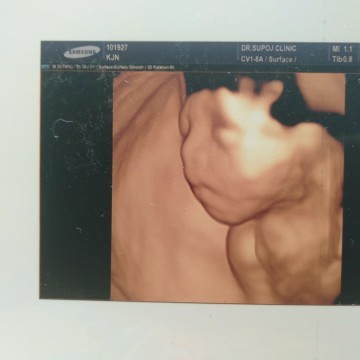

ขอดูของแม่ๆบ้านอื่นหน่อยค้ะ 26+4W ลูกสาวค่ะ

อยากซาวด์4มิติบ้างจัง เห็นหน้าลูกชัดมากเลยค่ะ